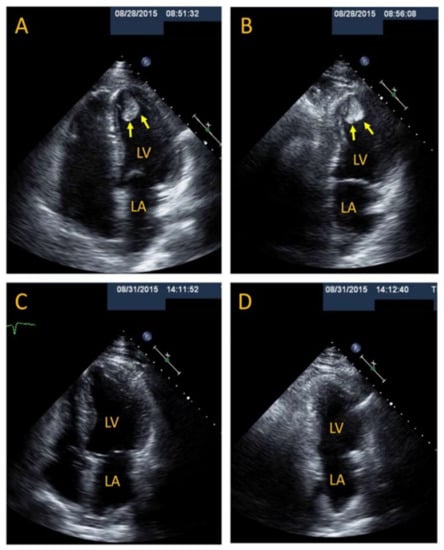

3.8. Thrombus and Prevention of Embolism in Patients with TTS